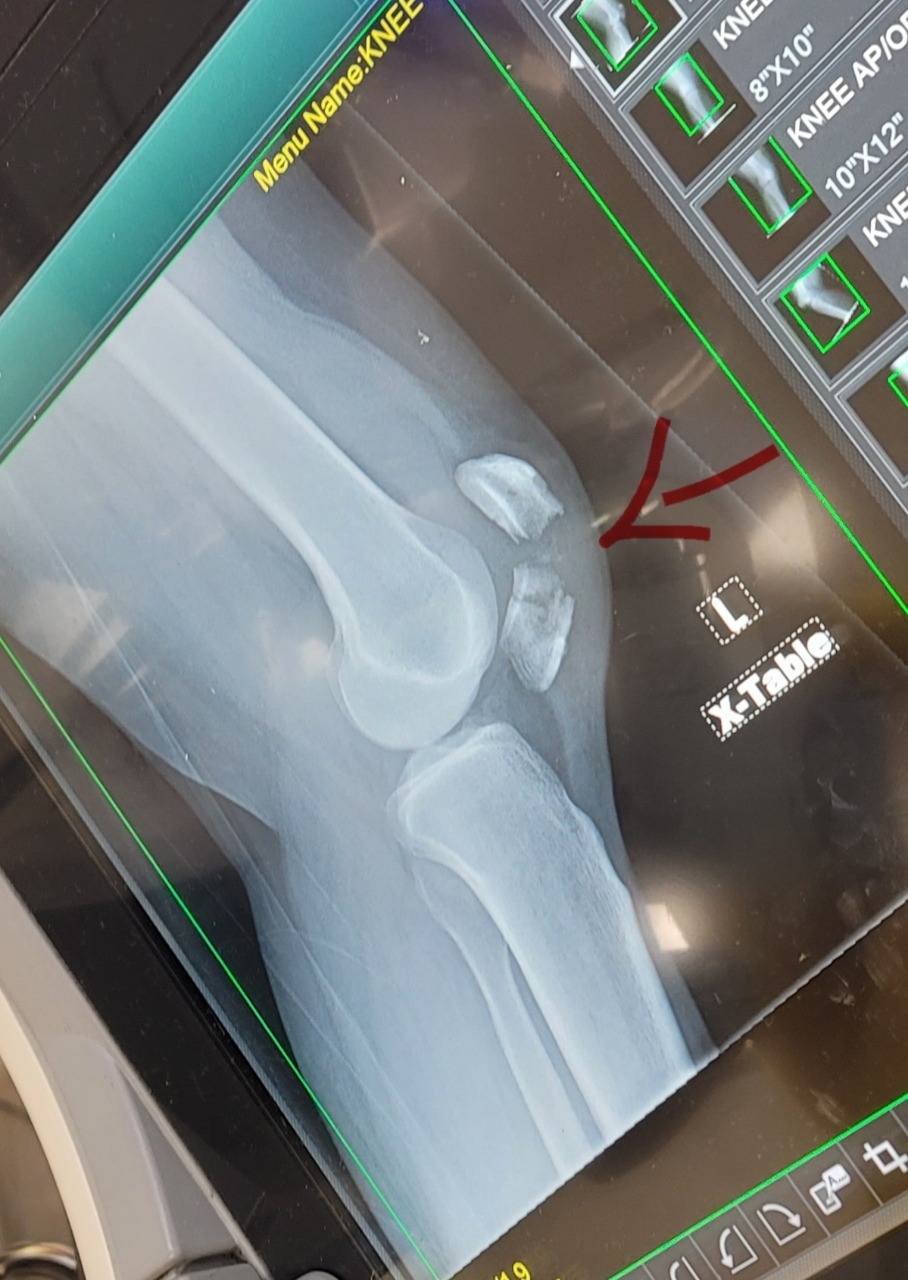

Maria was driving her husband to work using their only working vehicle when traffic ahead came to an abrupt stop. Despite braking as quickly as she could, a domino effect of cars stopping suddenly caused a collision. In a selfless act, Maria swerved and took the majority of the impact to protect her husband. While everyone else involved was thankfully unharmed, Maria suffered a severe injury, including a broken knee.

She was rushed immediately to the hospital, where doctors determined that her injury requires surgery. Maria will remain hospitalized for four days starting 1/20/26, followed by at least six weeks of recovery, and then ongoing physical therapy. During this time, she will be unable to work, will require 24/7 care, and will face mounting medical expenses, including surgery costs and copays.